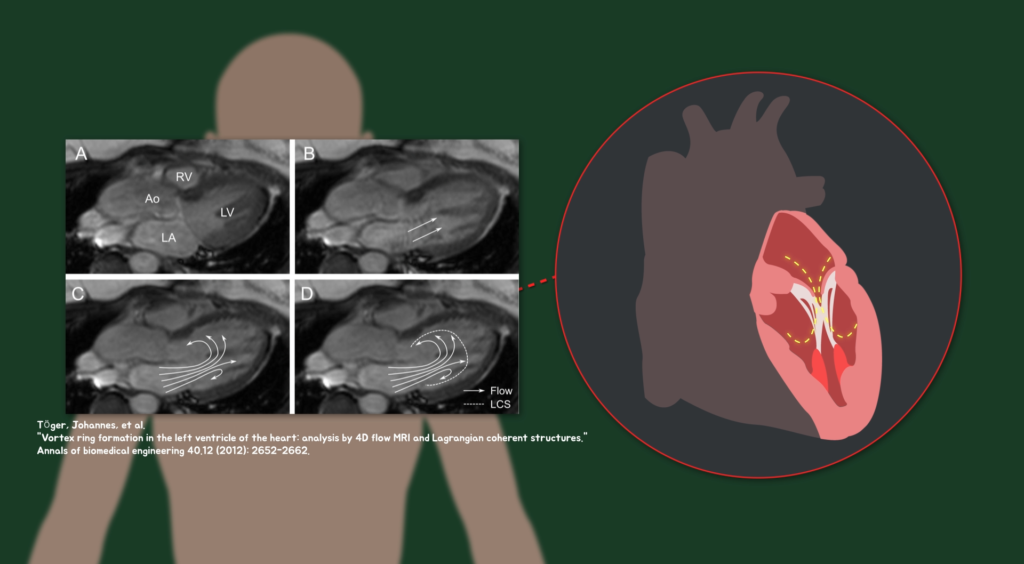

그리고 돌고래가 숨구멍을 활용해 물방울 고리를 만들며 놀 때도 관찰할 수 있고, 우리 몸속의 혈액 수송을 담당하는 심장에서도 좌심방에서 좌심실로 혈액이 흐를 때 와류 고리를 관찰할 수 있습니다. 궁금증이 해결되셨나요?